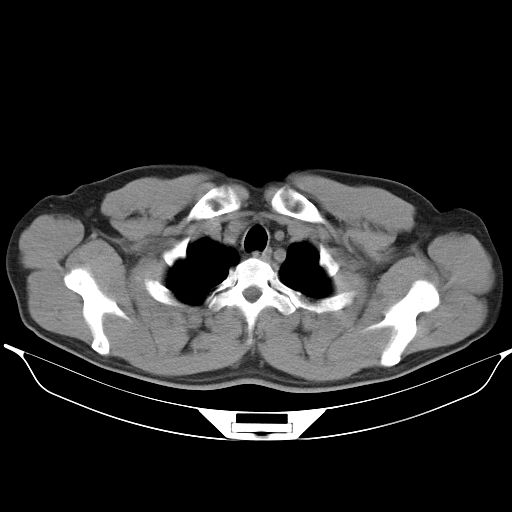

标题: CT25490:男,40岁,体检发现;无其它不适。 [打印本页]

标题: CT25490:男,40岁,体检发现;无其它不适。

支持 !考虑右下肺周围性肺癌并肺内多发转移,纵隔淋巴结转移,(气管前腔静脉后,隆突下,主动脉弓下都有了)